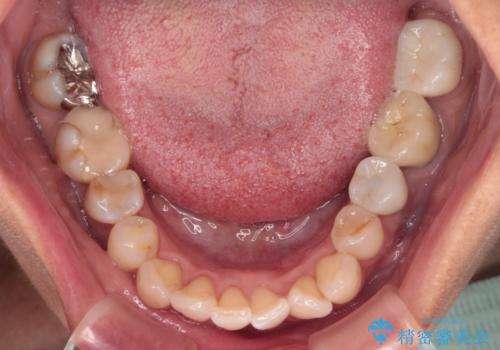

- 目立つ銀歯やむし歯、前歯のデコボコを気にして来院された患者様です。

デコボコはある程度改善できれば良いとのことでしたので、インビザラインの廉価版を用いて矯正治療を行うこととしました。

むし歯治療は、症状のある歯を矯正治療前に処置し、概ね歯列が整ったところで残りのは全て処置し、最後にインビザラインで歯列を仕上げることで、無駄なく治療を進めて行くこととしました。